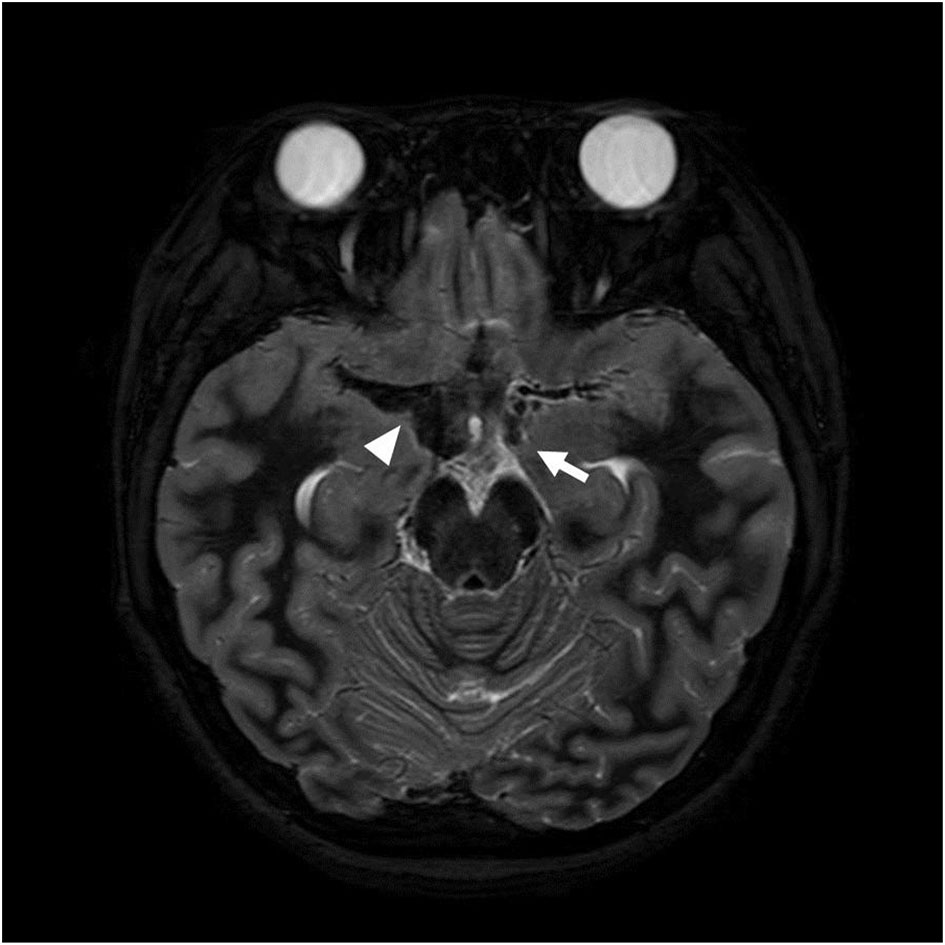

She was transferred to Samsung Medical Center with continuous alteration of mental status after the second seizure on the 12th day of hospitalization. On admission to this hospital, she was drowsy and sometimes confused. The patient consistently complained of severe headache. On the second hospitalization day, sudden weakness affecting both legs and dysarthria appeared. The symptoms waxed and waned during the day. On the third hospitalization day, her symptoms progressed into paraplegia and aphasia. Upon neurological examination, the Babinski sign and ankle clonus were positive bilaterally. The brain MRI on the day of transfer showed acute hemorrhage around the distal internal carotid artery (ICA) and right middle cerebral artery (MCA) obliterating the basal cistern and narrowing of both distal ICA and aneurysm at the left distal ICA (Figure 1). The brain MRI and magnetic resonance angiography (MRA) on the third hospital day demonstrated diffuse narrowing of bilateral MCAs, anterior cerebral arteries (ACAs), and distal ICAs, as well as small aneurysms at both distal ICAs (Figure 2D). In addition to the persistent SAH in the basal cistern and prepontine cistern, multifocal parasagittal acute infarctions were found (Figures 2A–C). Those findings raised the possibility of diffuse vasospasm associated with the SAH resulted from aneurysm rupture. The vessel wall MRI showed no contrast enhancement in the arterial wall, which could exclude the cerebral angiitis. Transfemoral cerebral angiography (TFCA) was performed on the sixth hospitalization day, revealing three unruptured aneurysms in both anterior choroidal arteries and left MCA and posthemorrhagic vasospasm involving both distal ICAs, MCAs, and ACAs (Figures 3A,F). The degree of narrowing of these cerebral blood vessels was severe for considering the endovascular coil embolization of the aneurysms. Therefore, we administered nimodipine and provided sufficient intravenous hydration to expand the vessels. On the seventh hospitalization day, after confirming that the vessels were widened enough to perform the intervention, we executed the first endovascular coil embolization for obliteration of unruptured aneurysms on the right anterior choroidal artery (Figures 3B–E). The upper motor neuron sign disappeared after the procedure. On the ninth hospitalization day, she became alert; however, the motor aphasia continued. She began to speak in sentences on the 15th day of hospitalization. On the seventeenth hospitalization day, we performed the second endovascular coil embolization for obliterating the left anterior choroidal artery aneurysm (Figures 3G–J). Although her brain MRI showed a slight reduction of infarction size compared to the previous results after the embolization, her clinical symptoms improved with the rehabilitation treatment. She was discharged on the forty-third hospitalization day without any motor deficit. The brain MRI and MRA performed 10 months after discharge demonstrated encephalomalacia in both parasagittal areas especially in the left frontal lobe (Figure 4). The electroencephalogram performed at that time showed epileptiform discharges in the left or right frontal areas. On her last follow-up in the outpatient clinic 14 months after discharge, her motor function was normal, and no neurologic deficit was observed.

Figure 1. Axial T2 weighted image obtained on the day of transfer shows low signal intensity (arrowhead) adjacent to the right middle cerebral artery (MCA) and an aneurysm at the left distal ICA (arrow) suggesting subarachnoid hemorrhage resulted from aneurysmal rupture.